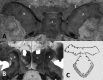

For a long time, because of its location at the skull base level, the sphenoid bone was rather mysterious as it was too difficult for anatomists to reach and to elucidate its true configuration. The configuration of the sphenoid bone led to confusion regarding its sutures with the other skull bones, its shape, its detailed anatomy, and the vascular and nervous structures that cross it. This article takes the reader on a journey through time and space, charting the evolution of anatomists' comprehension of sphenoid bone morphology from antiquity to its conception as a bone structure in the eighteenth century, and ranging from ancient Greece to modern Italy and France. The journey illustrates that many anatomists have attempted to name and to best describe the structural elements of this polymorphous bone.